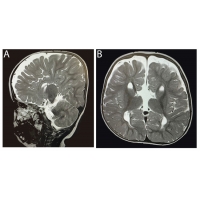

【佳学基因检测】17号染色体相关的额颞叶痴呆合并帕金森综合征基因解码、基

【佳学基因检测】17号染色体相关的额颞叶痴呆合并帕金森综合...